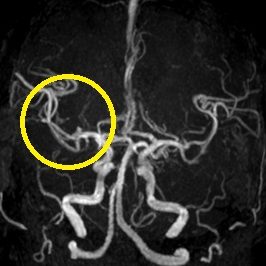

ろれつ困難と左半身重度麻痺のため当院に救急搬送となった患者様に対し、発症2時間30分でt-PAの投与を開始。t-PA開始1時間半後に左麻痺とろれつ困難は回復し始め、翌日には症状は消失。t-PA後のMRA検査で閉塞血管の完全再開通を認め、発症から2週間後に神経症状なく退院。

右大脳動脈閉塞(来院時MRA検査画像)

t-PA静注後